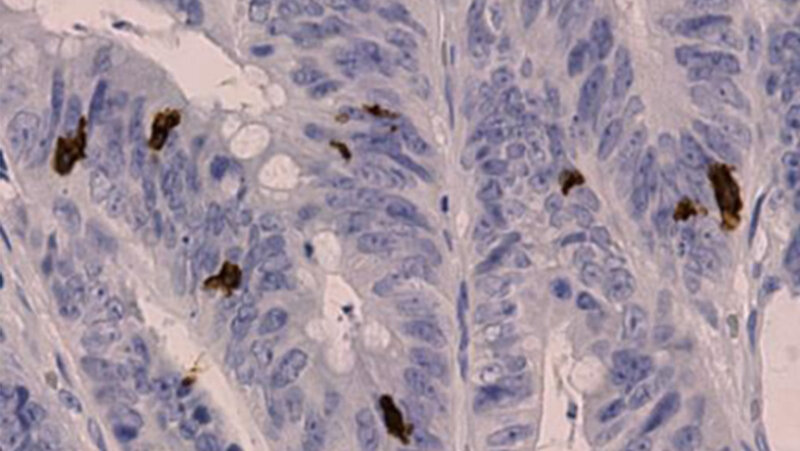

Immunzellen, die sich im Tumorgewebe aufhalten, können einen Aufschluss darüber geben, wie hoch die Überlebenschancen der Betroffenen sind. Die erworbene oder sogenannte adaptive Immunabwehr bekämpft Tumorzellen und andere Erreger. Dafür setzt das Immunsystem Immunzellen mit unterschiedlichen Funktionen ein. Die Art und Anzahl der Immunzellen, die sich im Tumor und seiner Umgebung aufhalten, sind ein Indikator dafür, wie effektiv die Tumor-Immunabwehr ist. Bisher gibt es jedoch keine Immunzell-basierte KI-Anwendung, die in der Klinik eingesetzt wird.

Um den KI-Algorithmus mit Hilfe von Deep Learning zu trainieren, haben die Wissenschaftlerinnen und Wissenschaftler über 300.000 mikroskopische Bilder von rund 1000 Betroffenen mit Dickdarmkrebs verwendet. Durch die Bildanalyse der verschiedenen Immunzellen konnte das Programm den AImmunoscore bestimmen und damit die Rezidiv-freie Überlebenschance vorhersagen. Die Genauigkeit des innovativen Modells lag dabei bei rund 80 Prozent. Mithilfe des Modells konnten die Forschenden die Patient:innen dahingehend einordnen, ob sie ein erhöhtes Risiko für einen Rückfall (Rezidiv) haben oder nicht.